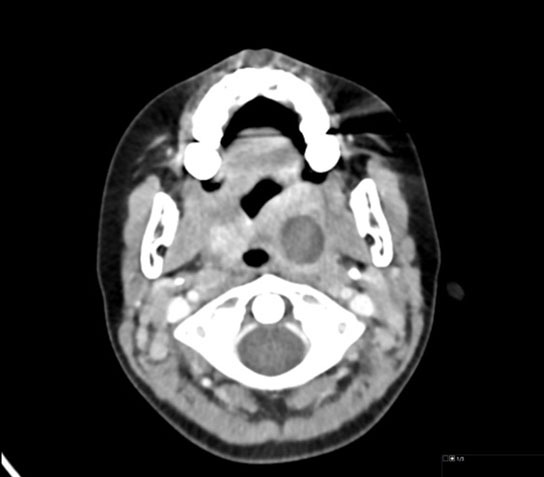

While the diagnosis primarily is clinical, a computed tomography (CT) scan of the neck with contrast may be used to determine the size of an abscess.23 Figure 7 shows CT scan findings of a peritonsillar abscess. Ultrasound is an alternative mode of imaging that does not involve any ionizing radiation.26 Imaging is not necessary, since studies have shown no difference in outcomes for patients treated with antibiotics compared to those who received aspiration or drainage of the abscess.27 However, CT scan may be considered if the diagnosis is not clear or the patient is not responding to medical management.26 Conversely, when there is a high suspicion of a peritonsillar abscess on physical exam, a CT scan does not typically add any additional information, and preferably could be avoided.26

Figure 7. Computed Tomography Scan of Peritonsillar Abscess |

![]() |

Axial contrast-enhanced computed tomography scan shows a 2 cm low-attenuation collection at the left tonsillar fossa, compatible with abscess (note the large but otherwise normally enhancing right palatine tonsil for comparison). Image used with permission from Mark Warren, DO, Dayton Children’s Hospital. |

An abscess that is larger than 2 cm may benefit from drainage; those of smaller size often are successfully managed with antibiotics alone.21 When ultrasound guidance is used, there is a higher rate of successful needle drainage.26